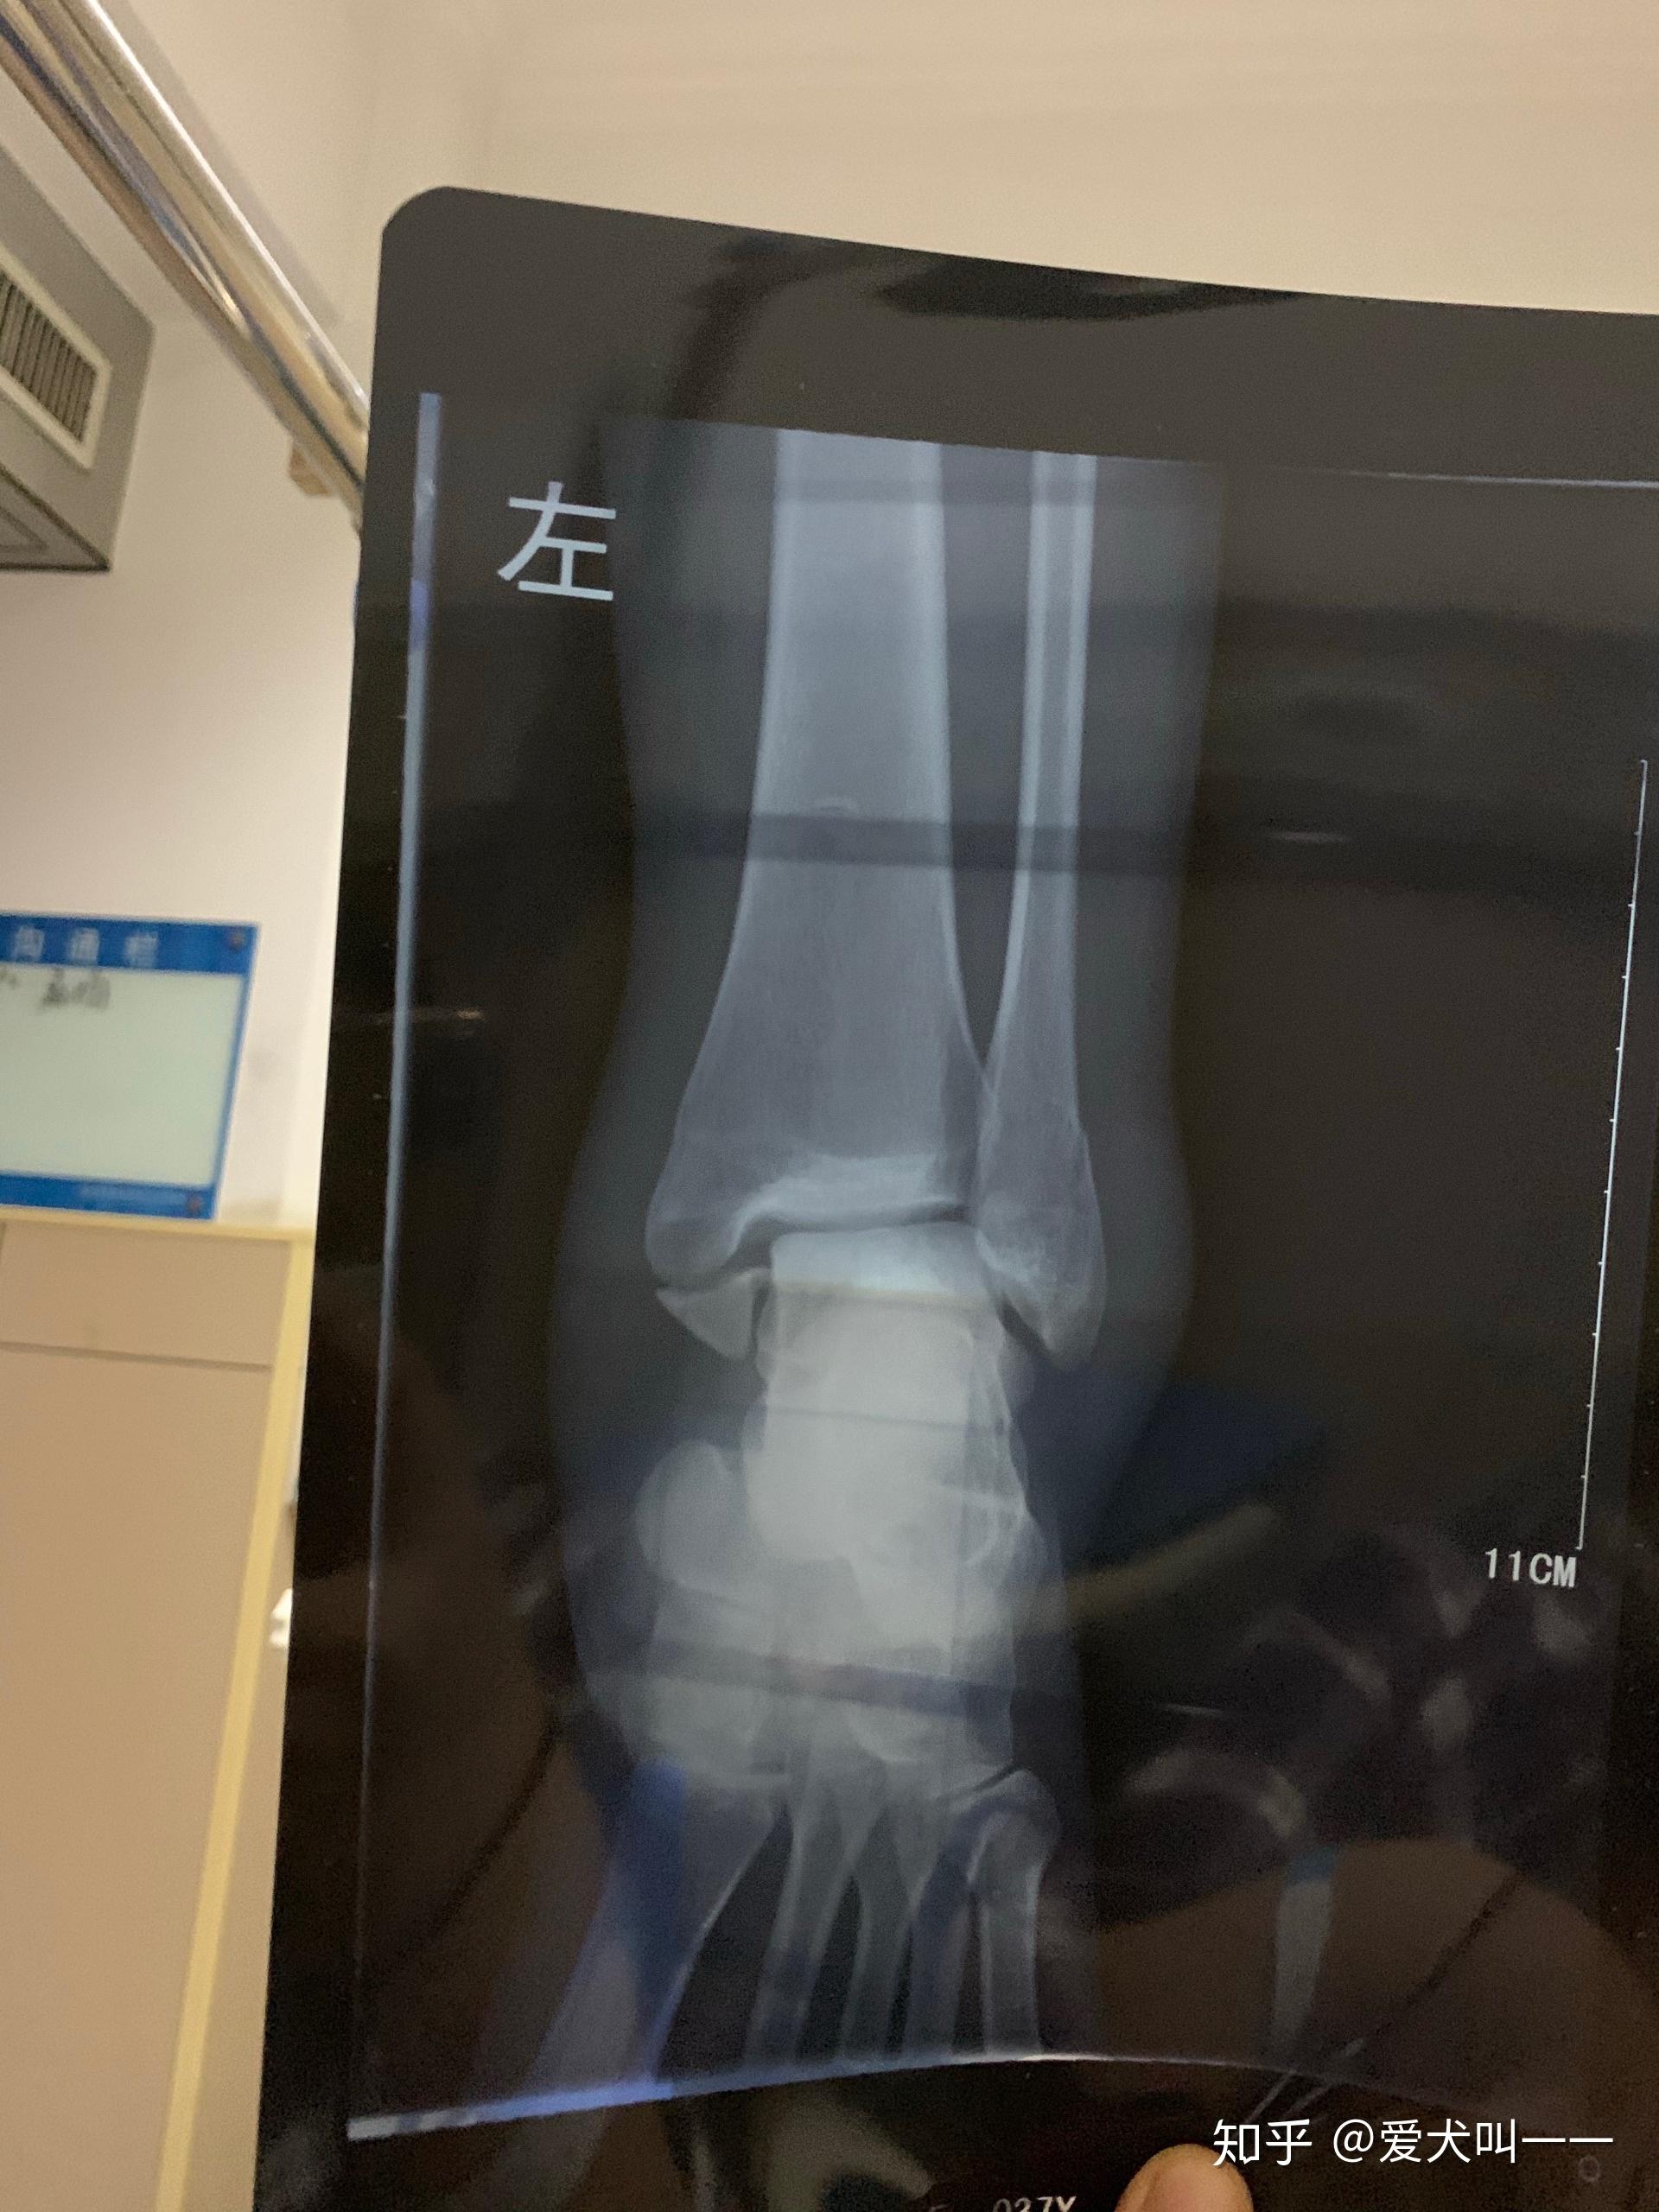

脚祼骨折记事 - 知乎

图片尺寸2048x1536